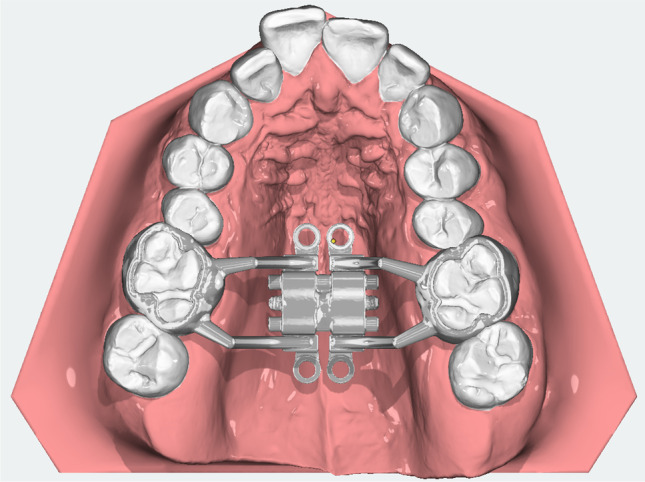

A fully digitally designed MARPE appliance was developed (see: Fig. 1) in a joint project by the Departments of Orthodontics and Oral & Maxillofacial Surgery with the intention of overcoming the design flaws of the existing MARPEs, such as the modified hyrax-type MARPE expander and the MSE.

Fig. 1.

Occlusal view of the digital D-MED design on intra-oral scan

The Dutch Maxillary Expansion Device (D-MED) (Orthoproof, Nieuwegein, the Netherlands) is an individualized, 3D-designed, and fabricated appliance based on an intra-oral scan (IOS) (TRIOS 3 scanner, 3Shape, Copenhagen, Denmark). It is designed with OnyxCeph3™ (Image Instruments, Chemnitz, Germany) and 3D-printed with the Concept Laser Selective Laser Melting printer (CADdent, Augsburg, Germany). The stainless-steel structure (alloy: 60.5% cobalt, 28% chrome, 9% tungsten, and 1.5% silicon) includes two bands around the upper first molars and four rigid connectors with circular screw holes (internal diameter: 2.2 mm, external diameter: 3.6 mm, height: 1.8 mm). The connectors are designed to follow the curvature of the palatal shelves with a clearance of 3 mm, while the screw holes are located at a distance of 2 mm from the palatal mucosa, with the aim of avoiding mucosal overgrowth. Four self-tapping miniscrews (Quattro®, PSM Medical Solutions, Gunningen, Germany) connect the device to the palate through the screw holes. The position of the miniscrews is planned perpendicular to the occlusal plane, at 2 mm paramedian to the midpalatal suture in order to avoid nose septum perforation, anteriorly at the level of the upper second premolars and posteriorly at the level of the upper second molars, at a distance of ca. 2 mm from the junction of the hard and soft palate (see: Fig. 2). Following 3D-printing, the base of an expansion screw (Forestadent, Pforzheim, Germany) is soldered on the structure. The screw is positioned parallel to the palate at the level of the upper first molars and has an expansion capacity of either 10 mm or 12 mm, selected according to the required maxillary expansion.